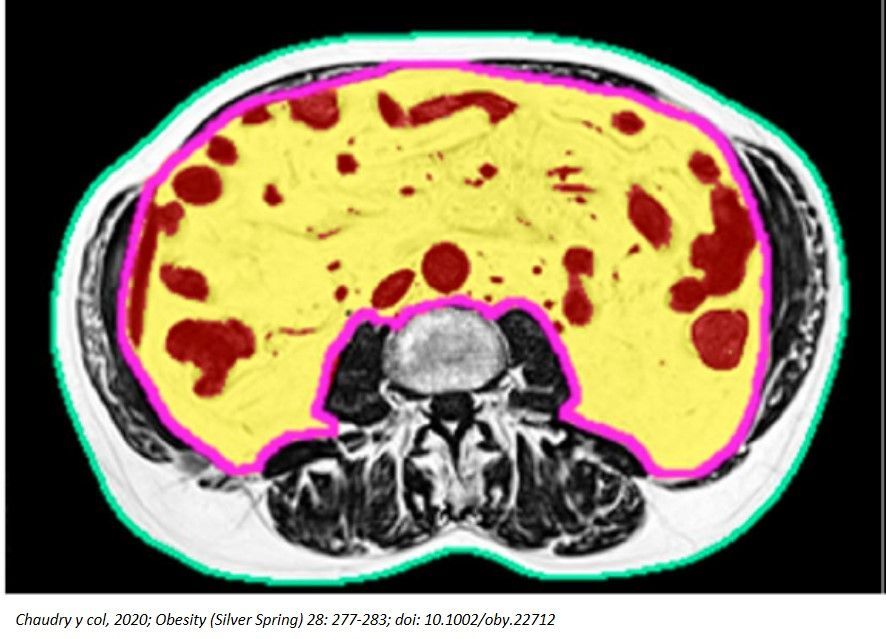

La valoración de la grasa visceral y abdominal tiene gran interés en el ámbito clínico al considerarse un factor de